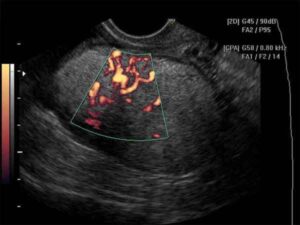

Nuovo trattamento contro il carcinoma ovarico